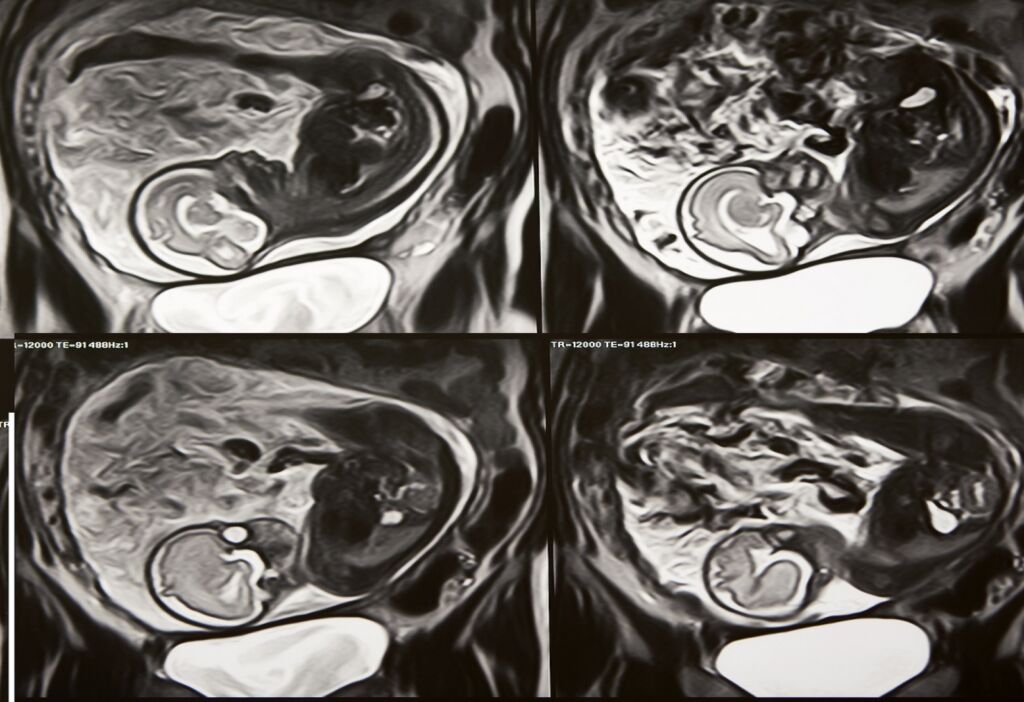

Fetal and Neo-natal

MRI of a pregnant woman

Some content here